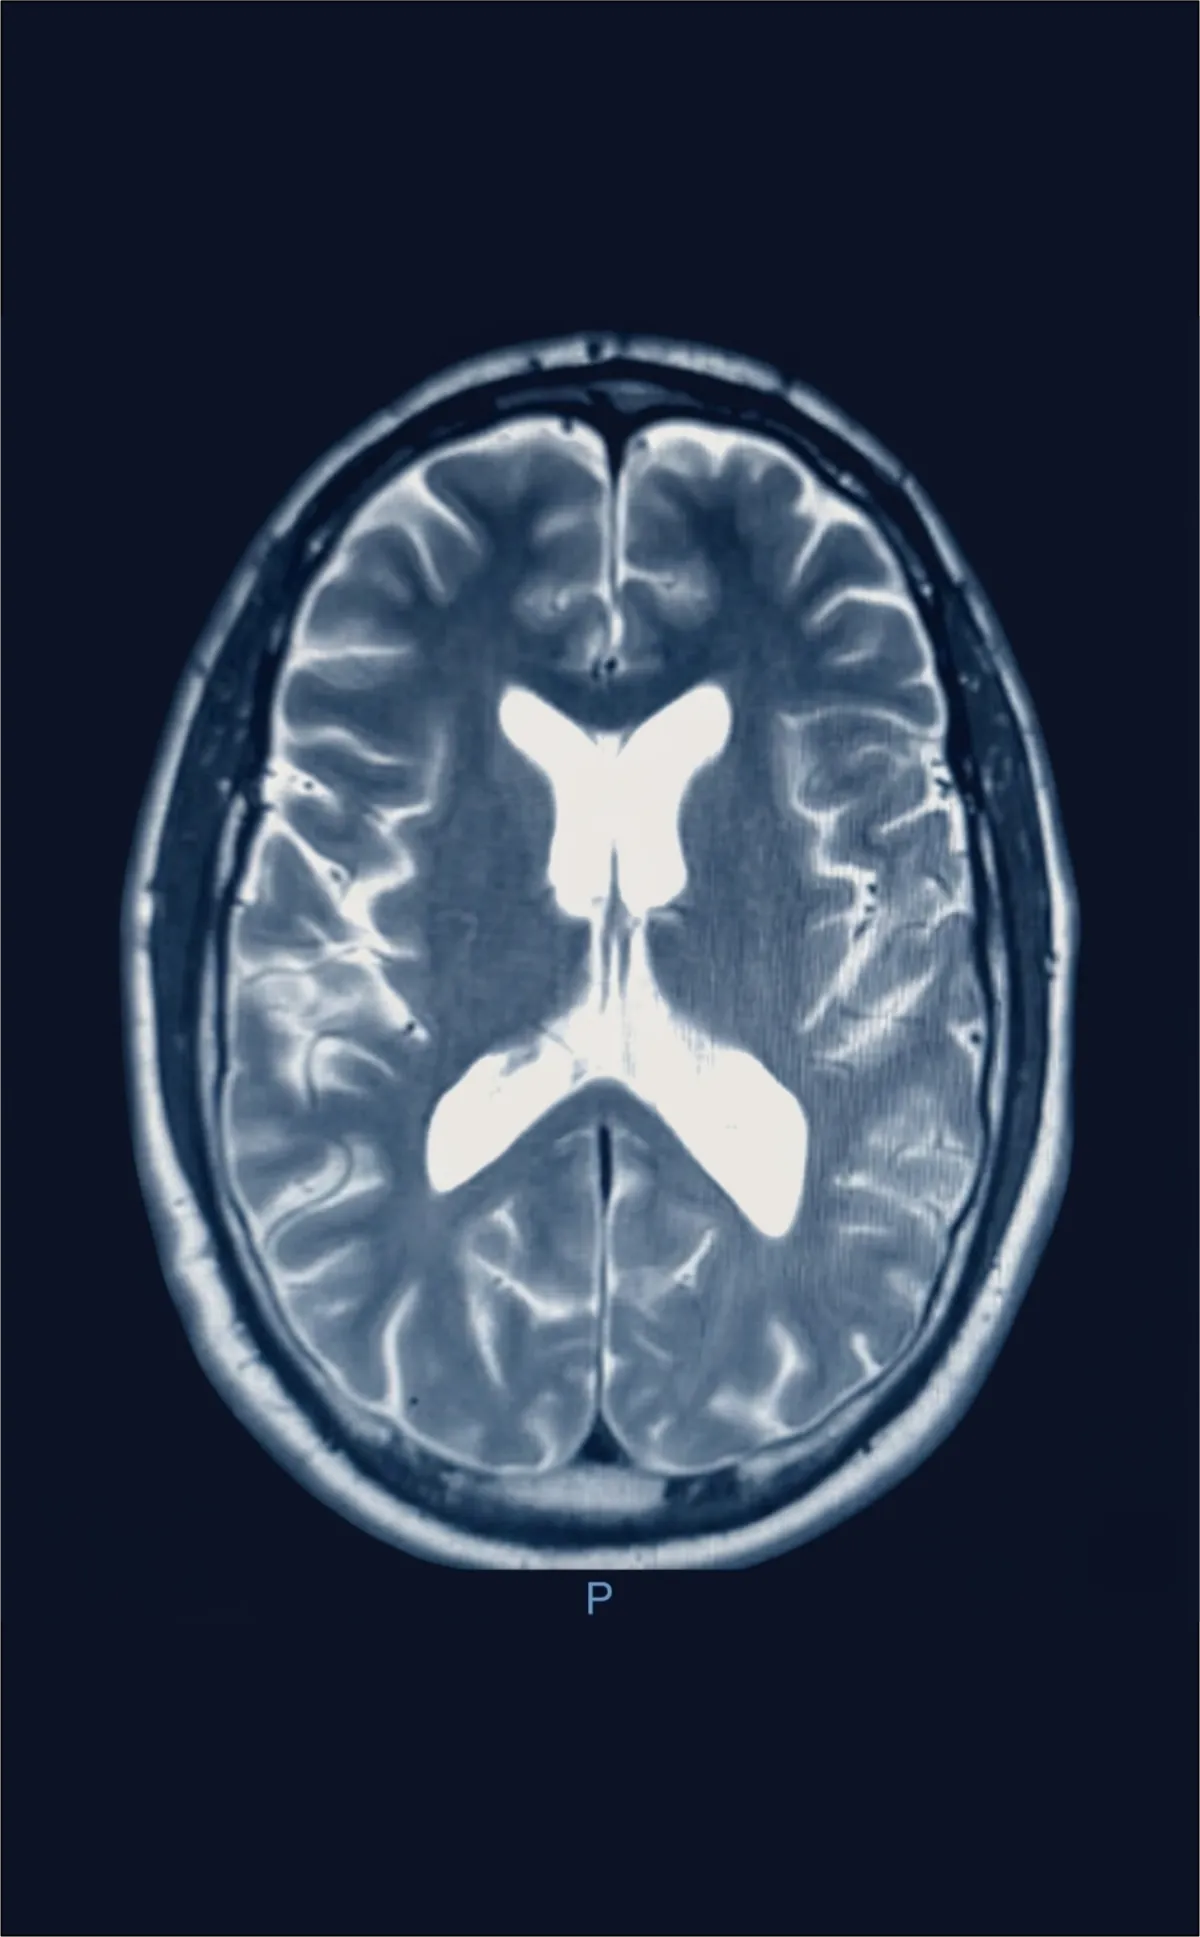

AI-Enhanced Cognitive Assessment

Brain Injury Analysis & Documentation

Platform analyzes brain imaging findings, correlates cognitive test results, and tracks symptom progression—all validated by board-certified physicians to support treatment planning and medical-legal documentation needs.